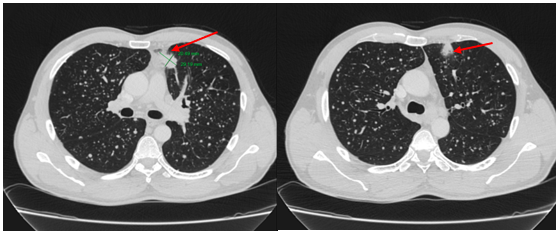

-         Chụp cắt lớp vi tính lồng ngực: phim trước điều trị

Hình 1. Trên phim chụp CT lồng ngực ở cửa sổ nhu mô: thùy trên phổi trái có khối đặc tròn bờ tua gai, kích thước: 29 x20mm, kính mờ và dày kẽ xung quanh, lân cận có nốt bán đặc kích thước 29 x 17mm, ngấm thuốc không đồng nhất sau tiêm, nghi ngờ có phần xâm lấn trung thất trước. Nhu mô thùy còn lại và nhu mô phổi phải lan tỏa các nốt đặc tròn to nhỏ không đều, đường kính: 2-8mm.

Hình 2. Cửa sổ trung thất: Vài hạch trung thất cạnh khí, hạch lớn nhất kích thước 14x7mm

-         Cắt lớp vi tính lồng ngực:

Sau 3 tháng điều trị đích:

U nguyên phát và u thứ phát ở cả 2 phổi đều giảm kích thước rất nhiều, không thấy hạch trung thất.

Sau 6 tháng điều trị:

U nguyên phát chỉ còn kích thước rất nhỏ, u thứ phát 2 bên phổi đã mất hết.